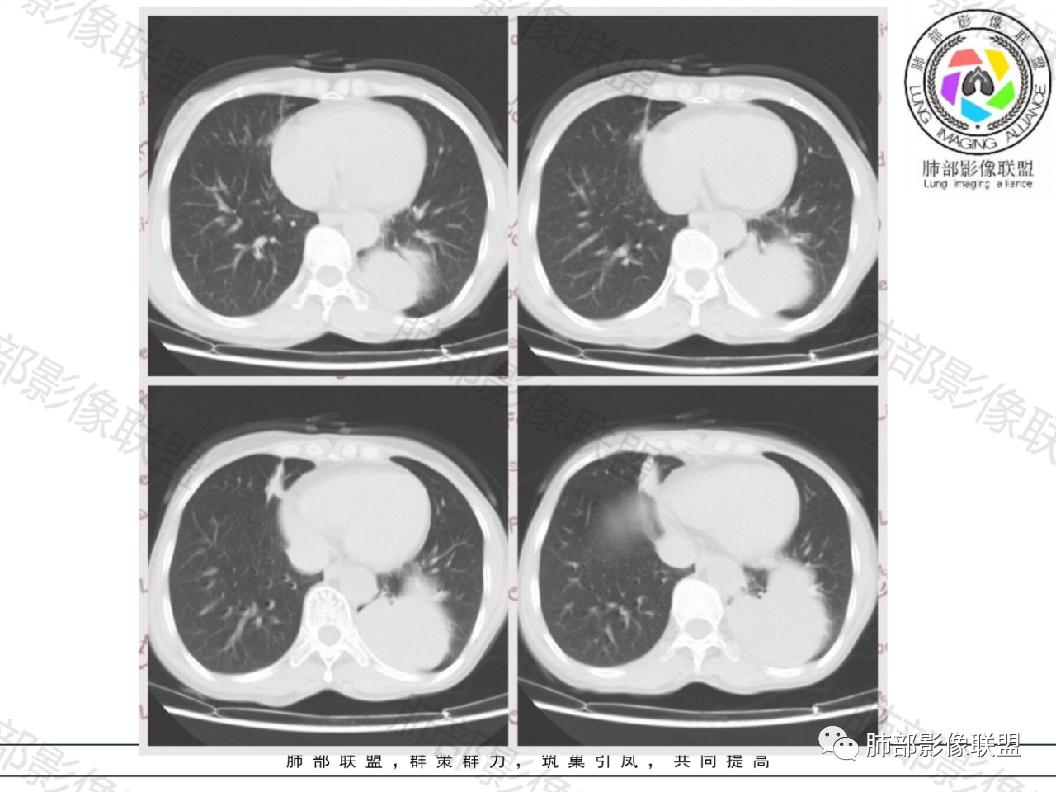

晨读:左肺下叶实性肿块,边缘光滑膨隆,近端支气管堵塞,远端宽基底与胸膜相连,部分胸膜下间隙消失,大肿块周围伴有多发小结节,小结节边缘光滑,平扫密度均匀,增强后不均匀强化,部分可见富血供强化,右肺下叶胸膜下条形实变影,收缩,右肺可能炎性病变,左肺下叶恶性肿瘤(癌肉瘤,肉瘤,鳞癌)

左肺下叶多发囊性病灶,有相通融合,有分隔线,增强无明显强化,考虑囊肿类病变

晨读病例,中年女性,体检发现病灶,左肺下叶多发囊性病灶,部分相通融合,内有分隔线,边界清晰,增强病灶无明显强化,考虑支气管囊肿或闭锁,神经节细胞瘤,其次感染性病变(结核)。

晨读:左肺下叶囊性肿块,边缘光滑膨隆,近端支气管堵塞,临近肺呈受压改变,与胸膜平行,近端多发小结节,小结节边缘光滑,似见轻度强化,血管贴边,内见分隔,考虑良性病变,支气管源性囊肿,结核或隐球

晨读:中年女性,无症状。胸部CT:左下肺后基底段肿块样病灶,边界清楚,患侧肺体积有减小。边缘光滑,囊性为主,可见分隔,相应肺段支气管未见,邻近肺受压,增强扫描强化不明显,仅有局部边缘强化,可能为支气管壁。个别层面似有肺外血管穿入。周围有散在小结节,形态、边缘、密度、强化一致。右下叶前基底段索条影。

考虑:支气管囊肿>肺隔离>CPAM>TB,鉴别Ca。